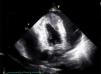

Case reportWe present the case of a 75-year-old Caucasian woman with a previous history of hypertension, dyslipidemia and a left total hip replacement. She was medicated with lisinopril-hydrochlorothiazide, bisoprolol and atorvastatin. Additionally, she was recently diagnosed with atrial fibrillation and was on warfarin. She had no previous symptoms of cardiac disease. She went to the emergency department of the local hospital due to nonspecific thoracic discomfort and malaise of over six hours duration associated with an episode of syncope. She also reported dyspnea on moderate exertion of two weeks duration. A complete blood count (CBC) and biochemistry revealed anemia and thrombocytopenia, with no other changes. The patient denied other signs or symptoms. Physical examination revealed a low-amplitude arrhythmic pulse, no heart murmurs and no signs of pulmonary congestion, blood pressure of 95/56 mmHg, heart rate of 101 beats per minute, and peripheral oxygen saturation of 85%. The CBC revealed anemia (Hg 8.9 g/dl) and thrombocytopenia (80 000 U/l). Biochemistry results revealed elevated serum cardiac troponin I (0.9 ng/ml; normal <0.04 ng/ml). A chest X-ray revealed a cardiothoracic index of >50% with widening of the mediastinum. The ECG revealed atrial fibrillation with ST-segment elevation in V2-V6, I and aVL. The patient was immediately transferred to a tertiary centre for emergent coronary angiography, which revealed a long stenosis of 50% in the mid-distal portion of the left anterior descending artery (with TIMI 3 flow) and a focal 30% stenosis in the mid segment of the right coronary artery (Figure 1). Left ventriculography revealed a hyperkinetic left ventricle and apical akinesia but otherwise normal systolic function. In the minutes after cardiac catheterization, the patient developed hypotension (systolic blood pressure of 85-90 mmHg) and slight chest discomfort persisted. An echocardiogram was performed and revealed a large pericardial effusion with diffuse thickening of the myocardium, mainly in the anterolateral wall and apex, which was assumed to be adherent fibrin (Figure 2). Due to worsening hemodynamic status and echocardiographic findings in a patient with chest pain, ST-elevation on the ECG and elevated cardiac troponin, cardiac rupture was suspected and the patient underwent urgent sternotomy and pericardiotomy with drainage of a large quantity of bloody fluid followed by hemodynamic recovery. The surgeons then identified a large unresectable tumor occupying the distal half of the anterior portion of the heart, which was biopsied (Figure 3). The patient was admitted to the cardiothoracic intensive care unit and was extubated on day 2 after surgery, and was then transferred to an intermediate care unit, with a favorable clinical status. A cervical-thoraco-abdominal-pelvic computed tomography (CT) scan was performed that identified myocardial tumor infiltration (measuring 6 cm×7 cm×11 cm) and pulmonary, cervical and abdominal wall metastases. The pathological study revealed a malignant mesothelioma. The immunohistochemical study documented diffuse expression of AE1/AE3, vimentin and MDM2 in tumor cells and focal expression of calretinin, EMA, podoplanin, desmin and p53 (Figure 4).

In several case reports the most common mode of presentation of pericardial mesothelioma was the development of pericarditis that evolved to constrictive pericarditis,9–11 sometimes associated with a circumferential pericardial effusion for which diagnostic pericardiocentesis was not conclusive.12 In the case presented, the clinical presentation was sudden, mimicking an anterior wall STEMI. The suspicion of left ventricular rupture was founded on the observation of a pericardial effusion, with a suspected large quantity of fibrin adjacent to the myocardium, associated with hypotension, indicating cardiac tamponade. As previously described, the sensitivity of echocardiography in the identification of pericardial mesothelioma is low,13 and CT scanning and MRI are preferable since these techniques not only detect invasion of adjacent structures and the presence of metastases but also, in the case of MRI, can assess the presence of constriction and ventricular dysfunction.6